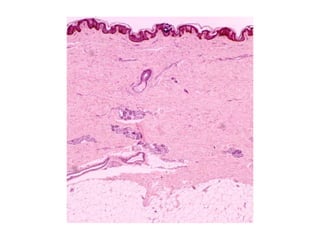

 La piel está constituida por dos estratos

 Los cortes de piel perpendiculares a la superficie

dejan ver abundantes evaginaciones digitiformes

de    tejido    conectivo,   llamadas     papilas

dérmicas, que empujan la parte profunda de la

epidermis.

Capas de la dermis

 La dermis papilar, la más superficial, consiste en

tejido conectivo laxo ubicado justo debajo de la

 Esta delicada red colágena contiene en forma

predominante moléculas de colágeno de tipo I y de

tipo III. De modo similar, las fibras elásticas son

filiformes y se organizan en una red irregular.

 Los vasos sanguíneos y las terminaciones nerviosas

sensoriales son bien visibles en las papilas

dérmicas.

 La dermis reticular es profunda con respecto a la

dermis papilar.

 Se caracteriza por tener gruesos haces irregulares

de fibras colágenas sobre todo de tipo I y fibras

elásticas mucho menos delicadas.

 Profunda con respecto a la dermis reticular hay una capa

de tejido adiposo, el llamado panículo adiposo, que

tiene un espesor variable.

 Esta capa y su tejido conectivo laxo asociado constituyen

la hipodermis o tejido celular subcutáneo.